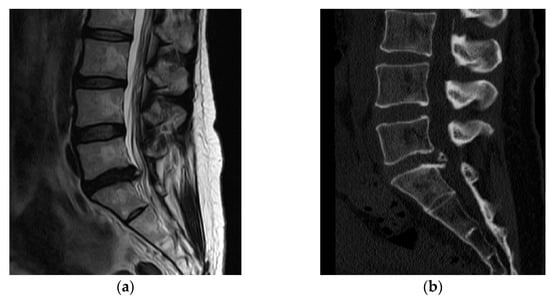

Eleven days after surgery, she was admitted to the emergency room due to severe pain in her back and left lower extremity. There was no clinical evidence of systemic infection (normal body temperature and no elevation of inflammatory marker) or wound problem (clear wound without local heating, redness, or discharge). MRI revealed no evidence of recurred or remnant disc. However, diffuse enhancement at the posterior epidural space from L4 to S1 levels and around the peridural space at the L5/S1 level (Figure 2) was noted. Conservative treatment, including root block, did not work; therefore, we decided to conduct revision surgery (L5/S1 posterior lumbar interbody fusion).

Figure 2.

Magnetic resonance imaging (MRI) was conducted to assess the recurrent pain in her back and left lower extremity at 11 days after surgery. (a) MRI revealed no evidence of recurred or remnant disc. (b,c) However, diffuse enhancement was noted at the posterior epidural space from L4 to S1 levels (arrows) and around the peridural space at the L5/S1 level (arrows).